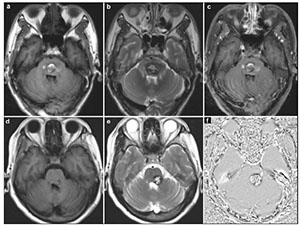

The surgical approach was designed according to the neurological examination and MRI (including diffusion tensor imaging (DTI), Figure 2). The 2-point method advocated by Spetzler and co-authors was employed in selecting surgical approaches[5, 7, 14, 15]. All the lesions were resected under electrophysiological monitoring including motor-evoked potential, somatosensoryevoked potential, and brainstem auditory-evoked potential. All of the operations were performed in park bench positions or supine positions. Totally, we applied the following 3 basic skull base approaches in handling the 20 BSCMs: midline suboccipital approach (14 patients), retrosigmoid approach (3 patients), and subtemporal approach (3 patients). As our experience with BSCMs has enriched, we advocate using simple and protective approaches instead of complex and invasive approaches. Spetzler et al. proposed that almost any BSCMs can be exposed adequately with one of the following basic skull base approaches or their variations: retrosigmoid, far lateral, midline suboccipital with or without telovelar, orbitozygomatic, and supracerebellar-infratentorial. We truly agree with their opinion but we believe that subtemporal approach could be performed in a minimally invasive way with lumbar drainage and protection of vein of Labbé.

| Figure 2 The surgical approach designed with the aid of DTI. T1-weighted (a) showed the lesion located in the right side of pontine. The three dimensional DTI (b) showed that the anterior and posterior side of the lesion was surrounded by tracts. The right approach to resect this lesion should be from the lateral side (we chose subtemporal approach). |